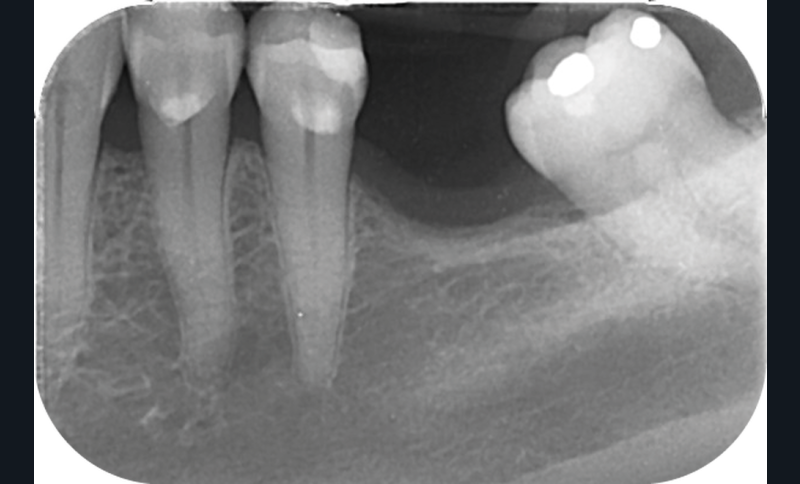

La perte d’une ou plusieurs dents entraîne la perte des points de contact, responsables de la stabilité et de la continuité de l’arcade. Par conséquent, une avulsion a pour première conséquence la migration ou la version d’une ou plusieurs dents distales (fig. 1 et 2). Cela est vrai en antérieur comme en postérieur.

L’âge de survenue de l’extraction semble avoir une importance sur l’apparition des migrations et des versions : si l’édentement intervient après 26 ans, les conséquences sont moins fréquentes [9].